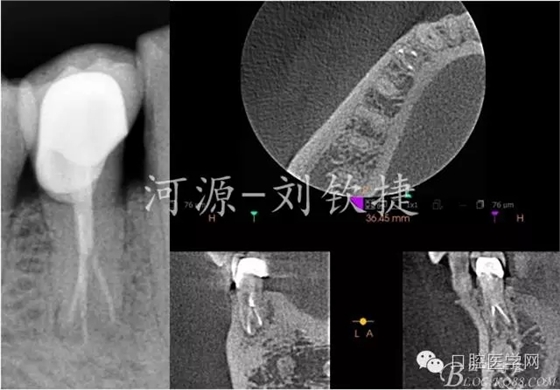

輔助檢查:X-Ray顯示44未做根管治療,根管影像在根中1/2突然消失,且明顯可見近遠根,根尖區(qū)有模糊陰影;拆除冠修復(fù)體后CBCT顯示44C型根管,頰側(cè)1根,舌側(cè)2根,頰側(cè)頸1/3白色影像達髓腔。可判斷最初就醫(yī)的原因是楔缺導(dǎo)致的牙髓炎。

4)復(fù)查X-Ray和CBCT;